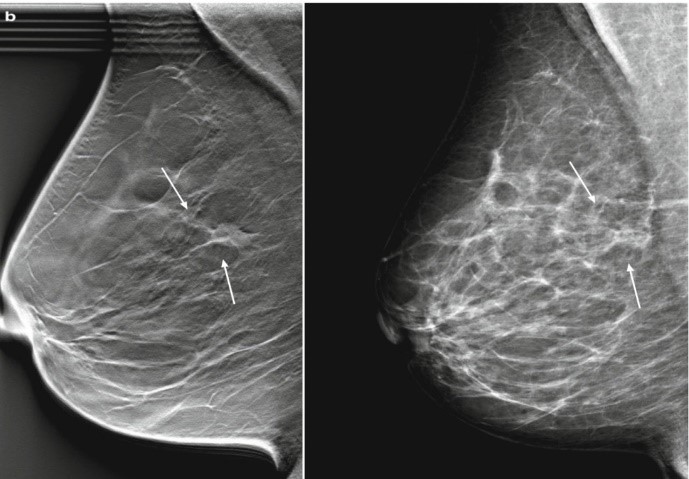

Hình ảnh minh hoạ tổn thương bờ tua gai của ung thư biểu mô thùy xâm nhập trên DBT (bên trái), nhưng lại không rõ ràng trên 2D (bên phải).